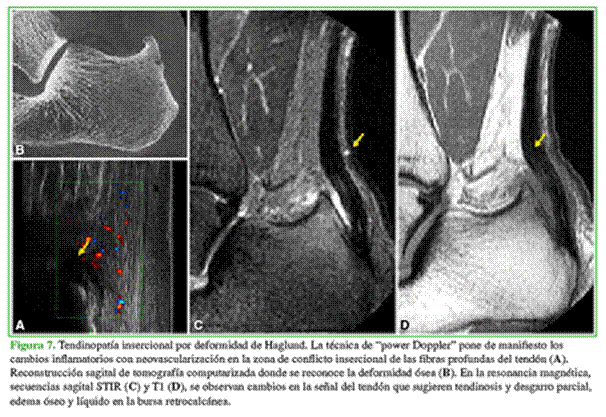

Un método poco solicitado en casos musculoesqueléticos y de mucha utilidad es la ecografía con técnica de “power Doppler”. Es más conocida su utilidad en reumatología para identificar y clasificar este tipo de enfermedades. Permite valorar el grado de vascularización de los tejidos tanto en la inflamación como en la fase de reparación. La ecografía con “power Doppler” permite hacer estimaciones precisas del flujo sanguíneo, incluso cuando los vasos son demasiado pequeños. También se la ha utilizado para demostrar hiperemia de tejidos blandos, sinovitis, para estudiar derrames articulares y colecciones. Los tendones morfológicamente normales no poseen flujo en la ecografía con “power Doppler”, ya que son estructuras hipovascularizadas.

Los desgarros muestran una señal baja en secuencia T1 y aumentada en secuencia T2. Lo mismo que los cambios inflamatorios en los tejidos blandos insercionales y periinsercionales (Figuras 7 y 8).